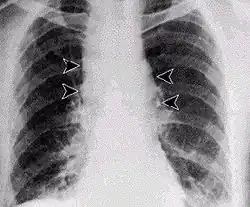

- Infecção pulmonar

A infecção pulmonar por carbúnculo provoca, nos primeiros dias, sintomas semelhantes aos da gripe, seguidos de problemas respiratórios graves, por vezes fatais. Se não for tratada, a infecção por inalação é a mais letal, com uma taxa de mortalidade de aproximadamente 90% a 100%. A infecção pulmonar também é conhecida por Doença de Woolsorter.